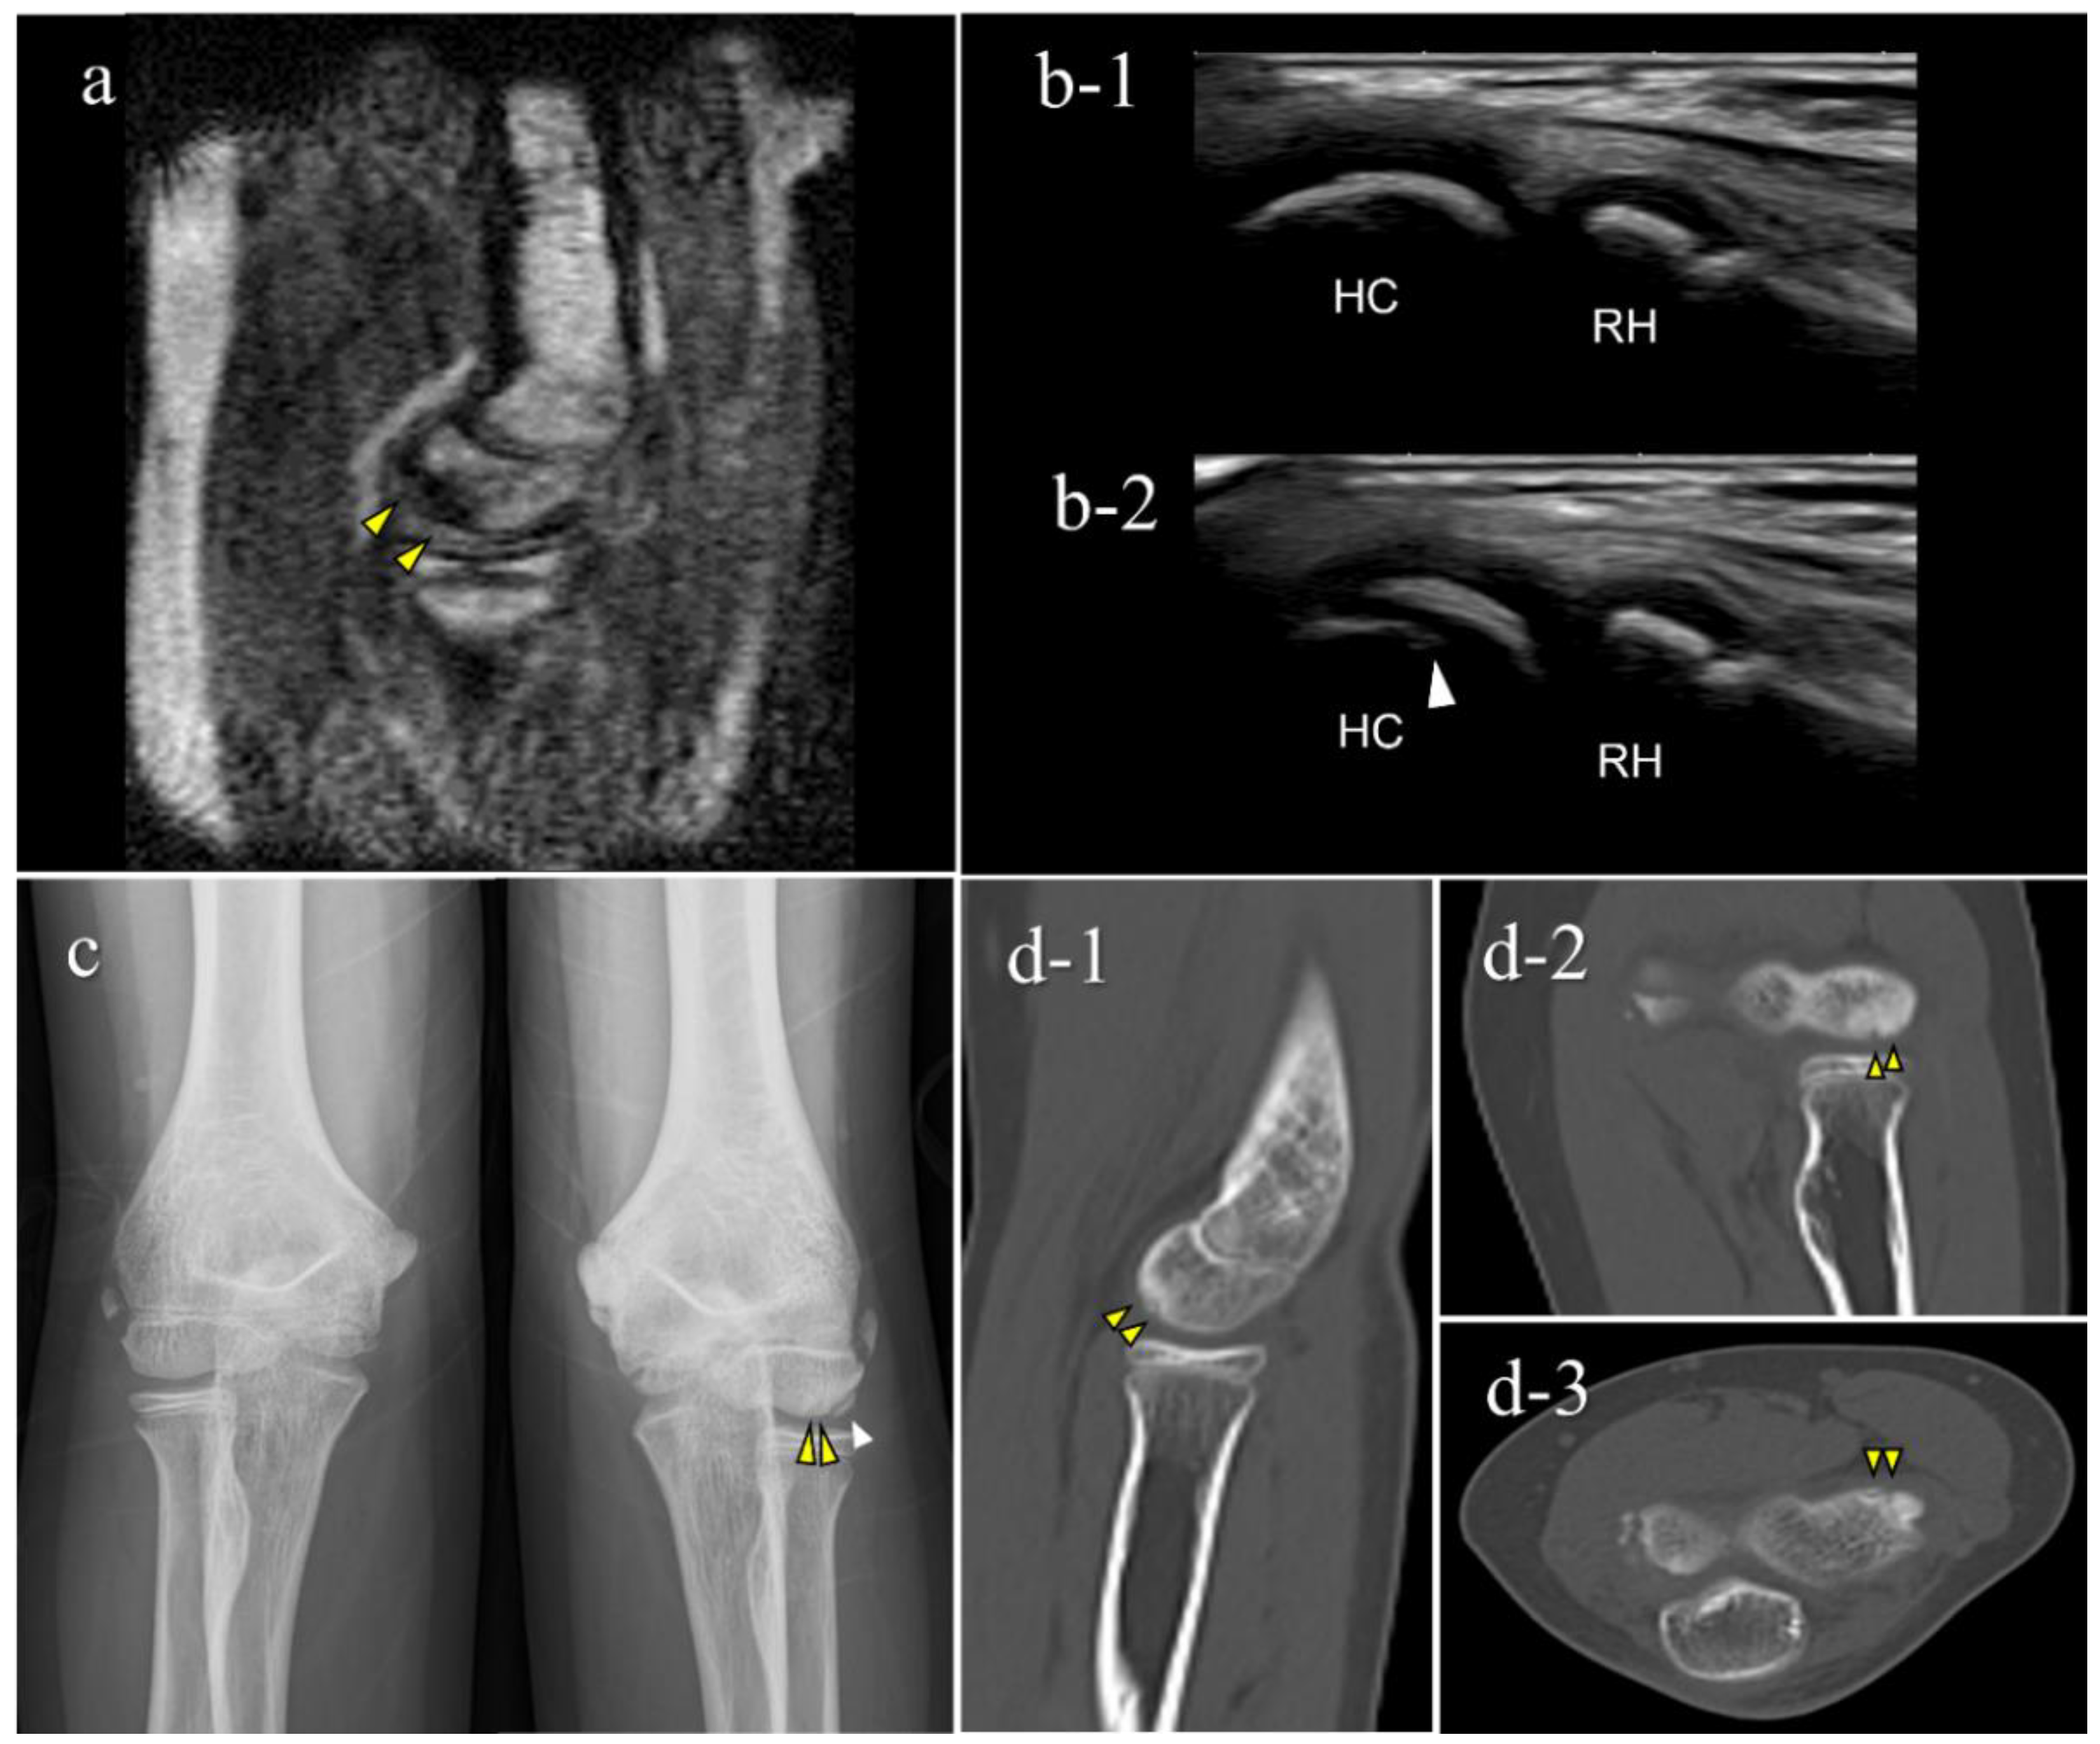

| 1 | 12 | M | - | − (1st) | + (B) | OCD | II | lateral | 15 |

| 2 | 11 | M | + | + (1st) | + (B) | OCD | I | central | 10 |

| 3 | 12 | M | - | + (2nd) | + (B) | OCD | II | central | 9 |

| 4 | 12 | M | + | + (2nd) | + (B) | OCD | II | lateral | 11 |

| 5 | 12 | M | + | + (2nd) | − (B) | OCD | I | central | 3.5 |

| 6 | 15 | F | - | + (2nd) | − (C) | not OCD | posterior | 3.5 | |

| 7 | 12 | M | - | + (2nd) | − (D) | OCD | I | central | 5.5 |